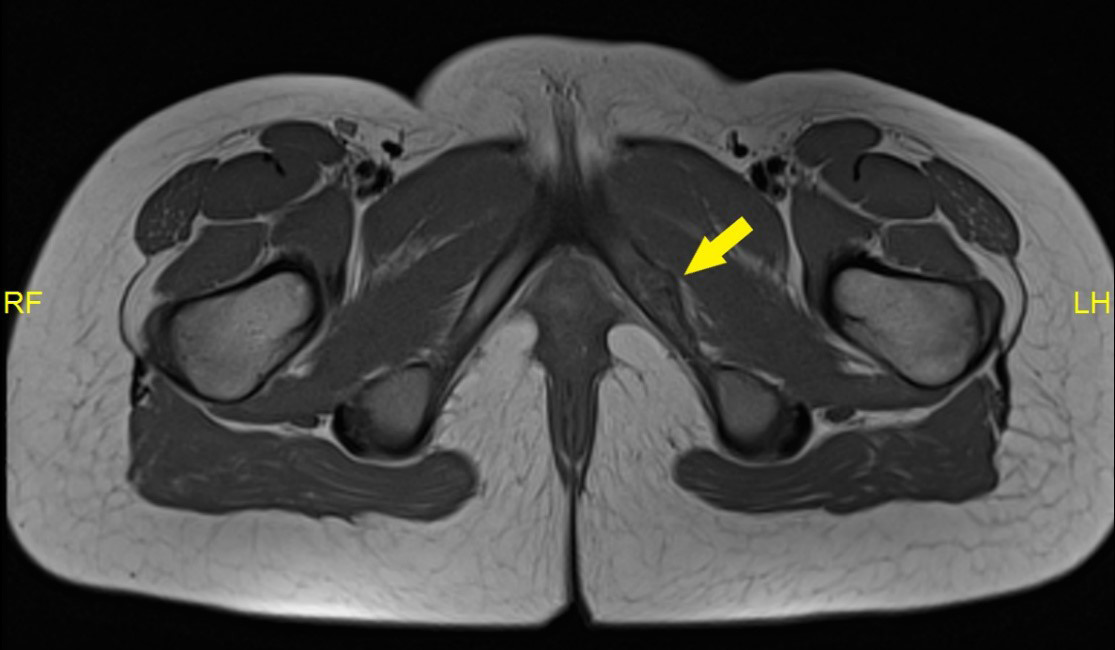

Given the pseudotumoral aspect was carried out magnetic resonance imaging (MRI) for the differential diagnosis with stress fractures, osteomyelitis and tumors. Axial image (proton density) PD (Figure 2) confirms widening of the SIP, as well as the irregularity of the same margins. In the STIR (short tau investment recovery) axial image (Figure 3), the left SIP presents a discrete hyperintensity inside, keeping a hypointense central band, and an edemain the corresponding adjacent bone marrow. This sequence overrides the signal intensity of bone marrow fat allowing you to more easily distinguish the bone edema.

Figure 2: RMN axial pelvis DP (protonic density). Widening ischiopubic synchondrosis, as well as the irregularity of ischiopubic synchondrosis, without associated soft parts component.